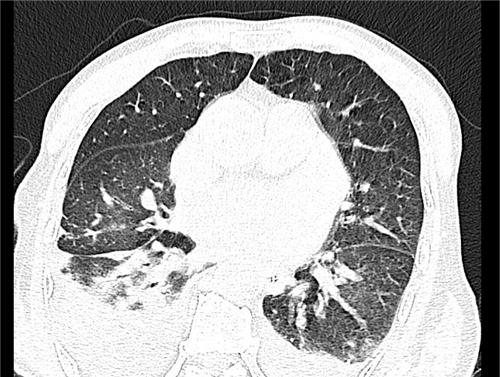

患者的胸部CT影像学资料

肺窗:双下肺可见斑片状渗出影及实变影